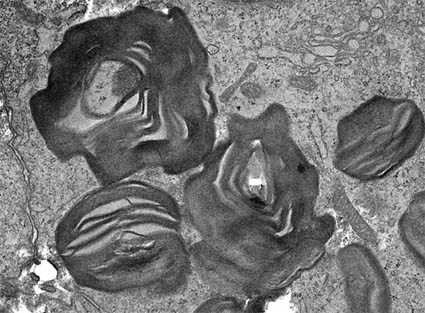

Electron Microscopy

There is osmophilic material, laminated, similar to myelin bodies; they are mainly found in podocytes, epithelium of Bowman's capsule, tubular epithelium and endothelium, although they can be seen in any type of cells. Myelin-like bodies have a periodicity of 4 to 10 nm.

Figure 16. Another image of GSL inclusions in podocytes. (Electron microscopy, original magnification, X8,000) .

Figure 17. Inclusion in podocyte of a woman with Fabry disease and severe clinical alterations. (Electron microscopy, original magnification, X8,000).